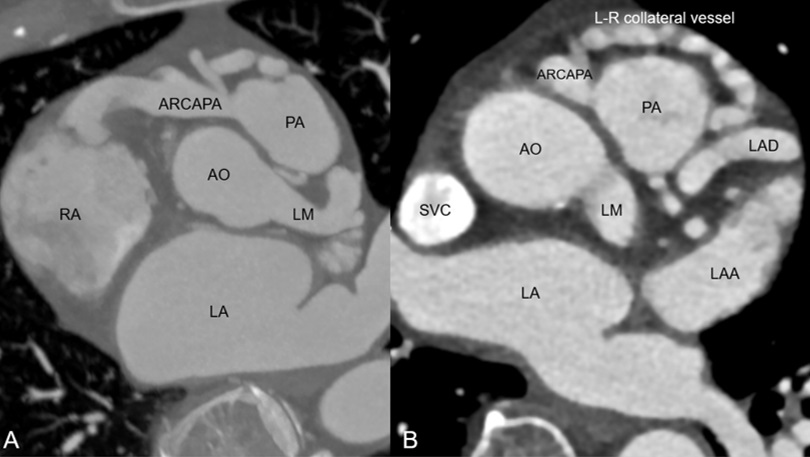

Selective left coronary angiography showed an ectatic left main artery and tortuous collaterals from the proximal left anterior descending (LAD) artery to a severely ectatic right RCA. The LAD was also severely ectatic and filled late. Retrograde filling of the pulmonary artery from the RCA was visualized (Figure 1, Video 1). We were unable to engage the RCA selectively with multiple diagnostic catheters. Ascending aortography confirmed absence of RCA ostium from the aorta and suggested the diagnosis of anomalous right coronary artery from pulmonary artery (ARCAPA) (Figure 2, Video 2). CT angiography confirmed ARCAPA with large left-to-right collaterals from LAD to RCA (Figures 3-5). There were no other congenital heart anomalies. Echocardiography showed normal biventricular function and normal chamber sizes. A myocardial perfusion Single Photon Emission Computed Tomography (SPECT) study showed a moderate intensity, medium-sized, partially reversible defect in the RCA distribution. The patient was referred to cardiothoracic surgery for consideration of reimplantation of the RCA to the aorta. However, due to her asymptomatic status at baseline, the decision was made to pursue initial conservative management.